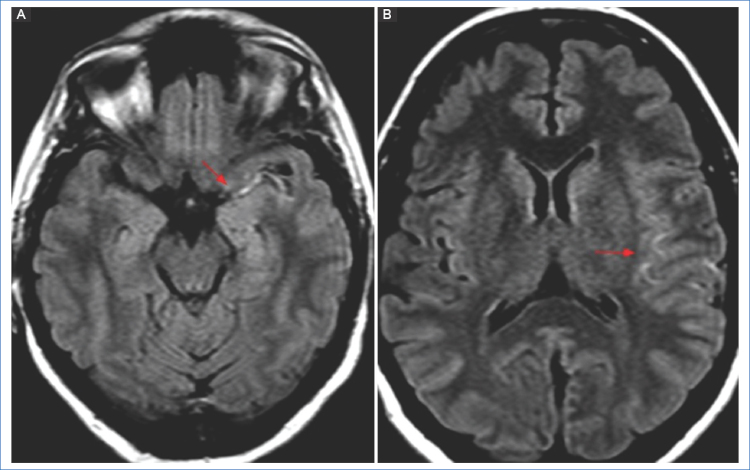

No obstante, a pesar de la alta sensibilidad de las secuencias de DWI, está descrito en la bibliografía que pequeñas lesiones ubicadas en el tronco encefálico con sintomatología leve (como la oftalmoplejía internuclear) pueden ser invisibles inicialmente5,7 (Fig. 3).

En la isquemia de origen cardioembólico se observan lesiones en múltiples territorios vasculares de manera bilateral, supra e infratentorial, o bien una lesión única distal cortical/subcortical5 (Fig. 4).

El foramen oval permeable (FOP) usualmente produce pequeñas lesiones corticales, únicas o múltiples, en la circulación vertebro-basilar, así como en el tálamo12 (Fig. 5).